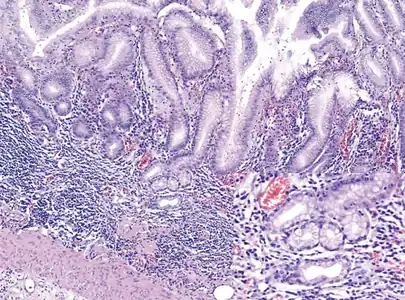

Histopathology of antral mucosa with atrophy. H&E 10x. Antral gastric mucosa with accentuated atrophy because of replacement by extensive intestinal metaplasia.